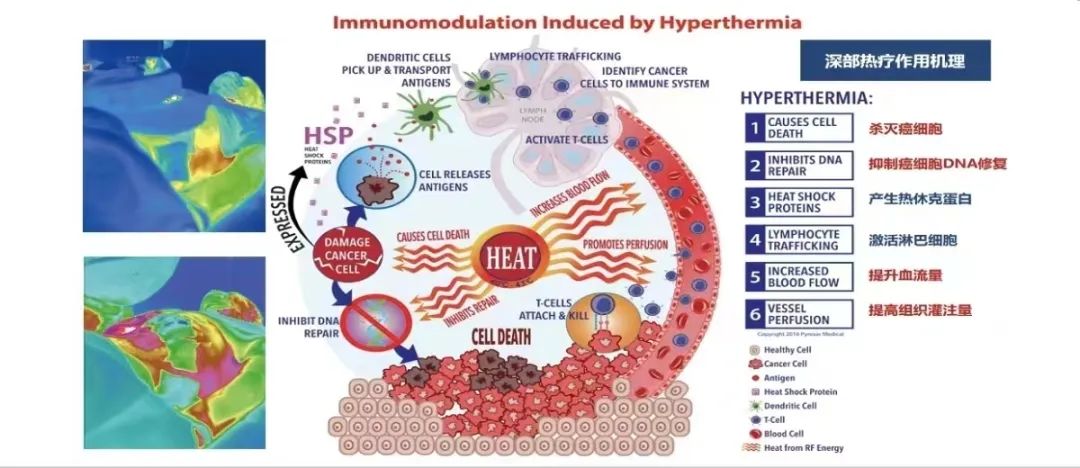

Hyperthermia: By heating the deep tissues in the target area to 43 degrees Celsius, protein denaturation occurs in cancer cells. Multiple treatments can lead to cancer cell apoptosis and alter the local tissue environment and metabolism, resulting in increased production of heat shock proteins and cytokines, thereby boosting immune activity.

The term “Hyperthermia” originates from the Greek word, meaning “high heat” or “overheating.” It refers to a treatment method in which different heat sources (radiofrequency, microwave, ultrasound, laser, etc.) are applied to raise the temperature of tumor tissues to an effective therapeutic level, causing tumor cell death while sparing normal cells from damage. Hyperthermia not only kills tumor cells but also disrupts the growth and reproductive environment of tumor cells.